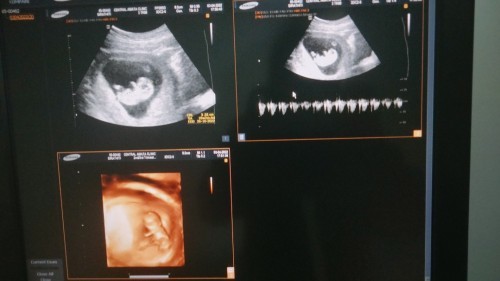

พอดีว่าท้องแล้วประกันสังคมอยู่ที่เอกชล ถ้าเราคลอดรัฐ เราจะเสียค่าใช้จ่ายไหมคะ ตอนนี้ประมาณ13w แต่อยากรีบศึกษาค่ะ เพราะว่าอยู่คนเดียว 💓ตื่นเต้นมากเลย